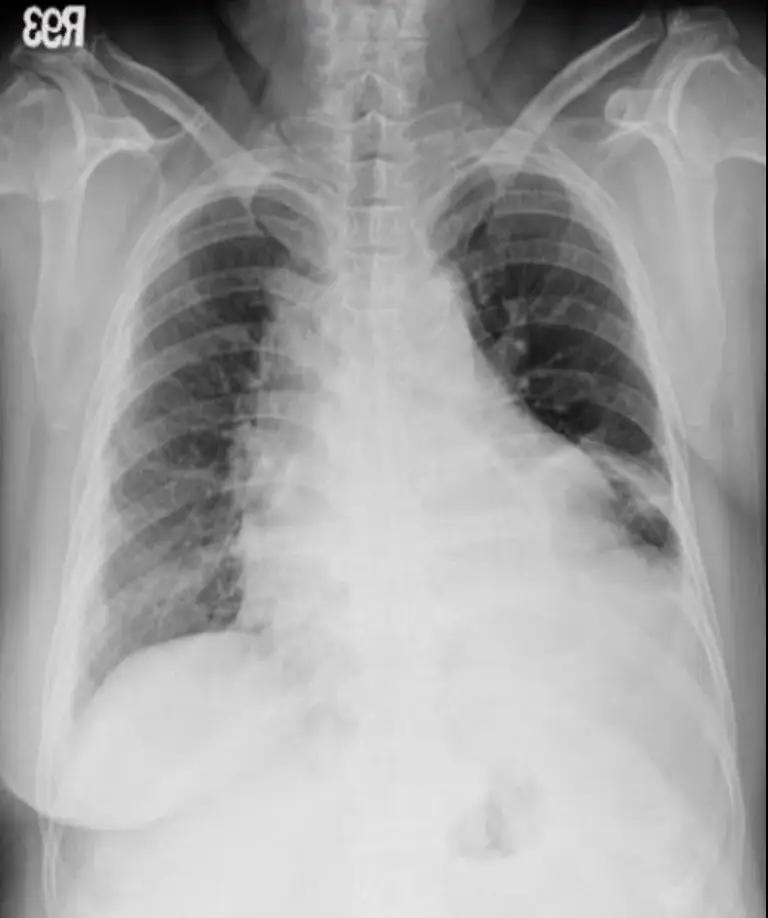

病人58歲婦女,主訴運動性呼吸困難、體重一星期間從84公斤增加至87公斤,雙腳水腫有一週之久,步 履難行,初步檢查呈現心臟擴大,乃前往醫學中心診療,在急診初步檢查Chest X-ray、心臟超音波和心 電圖(如圖),旋即住院。病人七年前有左乳癌經切除手術,至今並未完全緩解。病人近五年來,有高血壓 及糖尿病,都藥物治療中。生命徵象:T: 36.2°C, P:81/min, R:20/min, BP:150/84mmHg, Pain score:0。病 史詢問及身體理學檢查,請問下列何組心血管病理學檢查(Cardiovascular approach),是您應該觀察的標的? (1) 消沈的S1 and /or S2 (2) S3 and S4 (3) Pericardial friction (4) Mid-systolic murmur and pansystolic murmur (5) Kussmaul sign (6) Pulsating congestive liver 圖片描述 圖片描述 圖片描述 圖片描述

1. Chest X-ray:心臟邊緣呈對稱、光滑的「水瓶形」擴大,肺野未見肺靜脈鬱張或Kerley B線,提示為心包積液而非單純鬱血性心衰竭。(learningradiology.com)